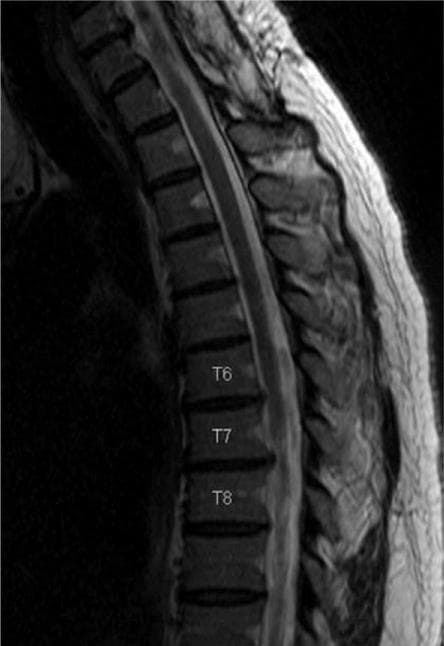

Лікування протрузій та гриж грудних міжхребцевих дисків

Протрузії та грижі грудного відділу міжхребцевих дисків зустрічаються рідше, ніж у шийному або поперековому відділах хребта. Однак, насправді, це трапляється не рідко.

Нами розроблена методика, що дозволяє успішно проходити голкою в потрібний міжхребцевий диск і проводити в центр його лазерний промінь. Дія лазерного променя така ж, як і при лікуванні шийних або поперекових дисків.